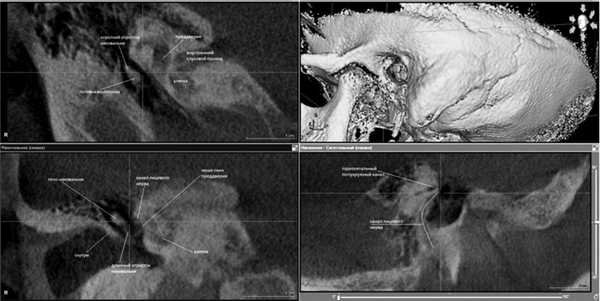

Пациент Н., 58 лет, с диагнозом: отосклероз, вовлекающий овальное окно, необлитерирующий, состояние после тимпанотомии в январе 2015 г., перелом длинного отростка наковальни. Ранее пациенту была выполнена попытка стапедопластики на левом ухе, в ходе тимпанотомии произошел перелом длинного отростка наковальни, оперативное вмешательство было прекращено. При поступлении в ЛОР-клинику ПСПбГМУ были выполнены микроотоскопия (барабанная перепонка левого уха серая, рубцово изменена), акуметрия (шепотная и разговорная речь на левое ухо 0 м, опыт Вебера с латерализацией влево, опыт Ринне отрицательный с двух сторон), тональная пороговая аудиометрия (повышение порогов слуха по смешанному типу с преобладанием кондуктивного компонента, костно-воздушный разрыв до 80 дБ, повышение порогов слуха по кости в диапазоне от 20 до 30 дБ), КЛКТ височных костей (рис. 1).

Рис. 1. Больной Н., 58 лет. КЛКТ височных костей. MPR/рентгенологическое исследование. Во фронтальной и сагиттальной плоскостях отмечены контуры наковальни (перелом), в сагиттальной плоскости обозначен ход канала лицевого нерва.

Заключение по КЛКТ левой височной кости: пневматический тип строения сосцевидного отростка, пневматизация клеток не нарушена, антрум обычных размеров, пневматизирован. Барабанная полость пневматизирована, слуховые косточки четко визуализируются, нарушена целостность длинного отростка наковальни (определяется линия перелома). Ниша овального окна: уменьшен размер просвета, склерозирована, прямоугольной формы. Признаки рубцового процесса в области окна улитки. Структуры внутреннего уха - без особенностей.

Пациенту была выполнена стапедопластика на левом ухе. Интраоперационные находки: слуховые косточки окружены рубцовой тканью, четко определяется уровень перелома длинного отростка наковальни, который был фиксирован лишь рубцовой тканью, стремя с истонченными ножками полностью фиксировано к окружающим костным стенкам и подножной пластинке, ниша овального окна узкая и глубокая. После установки тефлонового протеза было получено улучшение слуха - разговорная речь 4 м (до операции 0 м).

Заключение по КЛКТ правой височной кости: пневматический тип строения сосцевидного отростка, пневматизация не нарушена, антрум обычных размеров. Барабанная перепонка истончена. Барабанная полость пневматизирована, слуховые косточки с явлениями декальцинации, подножная пластинка стремени утолщена, кальцифицирована, определяется нависание канала лицевого нерва над нишей овального окна, костная капсула его частично не прослеживается. Структуры внутреннего уха без особенностей (рис. 2).

Рис. 2. Больная Ж., 45 лет. КЛКТ височных костей. MPR/рентгенологическое исследование. В сагиттальной плоскости обозначен ход канала лицевого нерва, во фронтальной - расположение канала лицевого нерва над нишей преддверия.

Пациентке была выполнена стапедопластика на правом ухе. Интраоперационные находки: фиксация подножной пластинки стремени в нише овального окна, глубокая ниша овального окна, нависание канала лицевого нерва, рубцовая ткань вокруг ниши овального окна. После установки тефлонового протеза получена прибавка слуха: разговорная речь до 6 м, шепотная речь до 3 м.